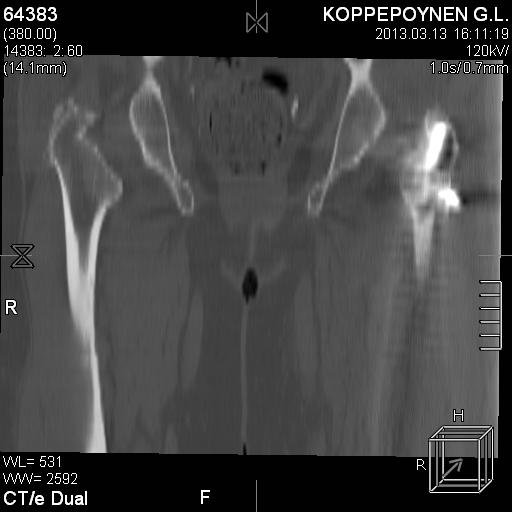

Делали КТ после операции.

Непонятно, на какой вопрос с помощью КТ хотели получить ответ? IMHO это было ненужное исследование, все проблемы были видны на обычном снимке. А что на второй проекции? Где аксиальная или профиль?